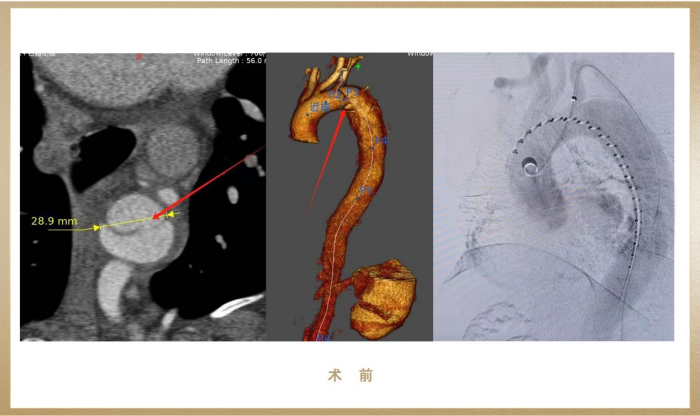

患者为一名37岁藏族男性,因剧烈胸痛紧急入院,术前CTA提示Stanford B型主动脉夹层,破口近左锁骨下动脉,夹层动脉瘤最大径达38mm,一旦破裂会在短时间内引发大出血、休克甚至死亡,情况十分危急!

(图:术前影像)